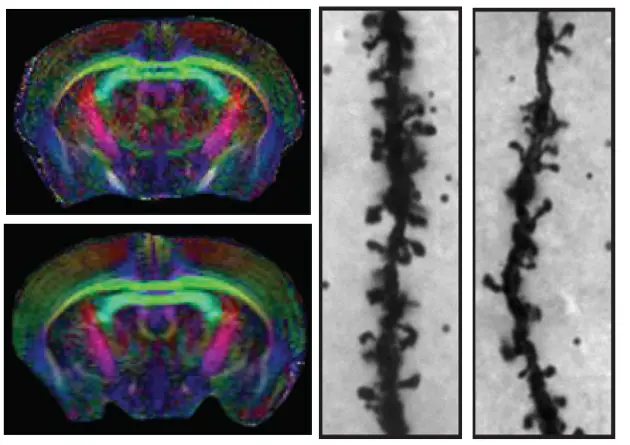

We have recently shown how several genes encoding proteins belonging to the nerve growth inhibitory Nogo signaling system are regulated to influence structural synaptic plasticity and the formation of lasting memories. Ongoing studies using transgenic animals aim at understanding molecular mechanisms behind the formation of lasting memories and causes of memory disorders, as seen e.g. in aging.

Overexpression of Nogo receptor 1 (NgR1) in forebrain neurons does not affect gross brain anatomy but inhibits the formation of dendritic spines.